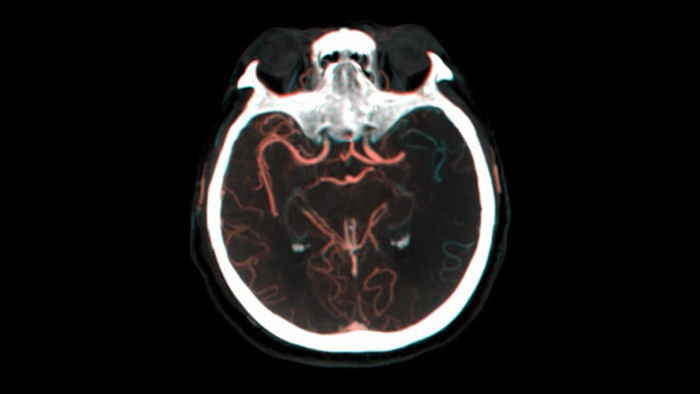

SmartCT Vaso IV

Compruebe la ubicación y la longitud de un coágulo

SmartCT Vaso permite la visualización más allá del coágulo con la adquisición de imágenes periprocedimiento de los aspectos del vaso distal en el accidente cerebrovascular isquémico. SmartCT Vaso es una técnica de adquisición basada en una exploración por TAC de haz cónico y una inyección de contraste intraarterial. Mediante la repleción retrógrada, las estructuras de los vasos antes y después del coágulo se vuelven visibles. Además, SmartCT Vaso 3D Roadmap puede utilizarse para visualizar dispositivos de recuperación de coágulos.

Ver la repleción colateral

Visualización de la repleción colateral

Dual View permite visualizar  los volúmenes de TAC de haz cónico de fase temprana y tardía yuxtapuestos mejorando la identificación de penumbra y la visualización de la repleción colateral.